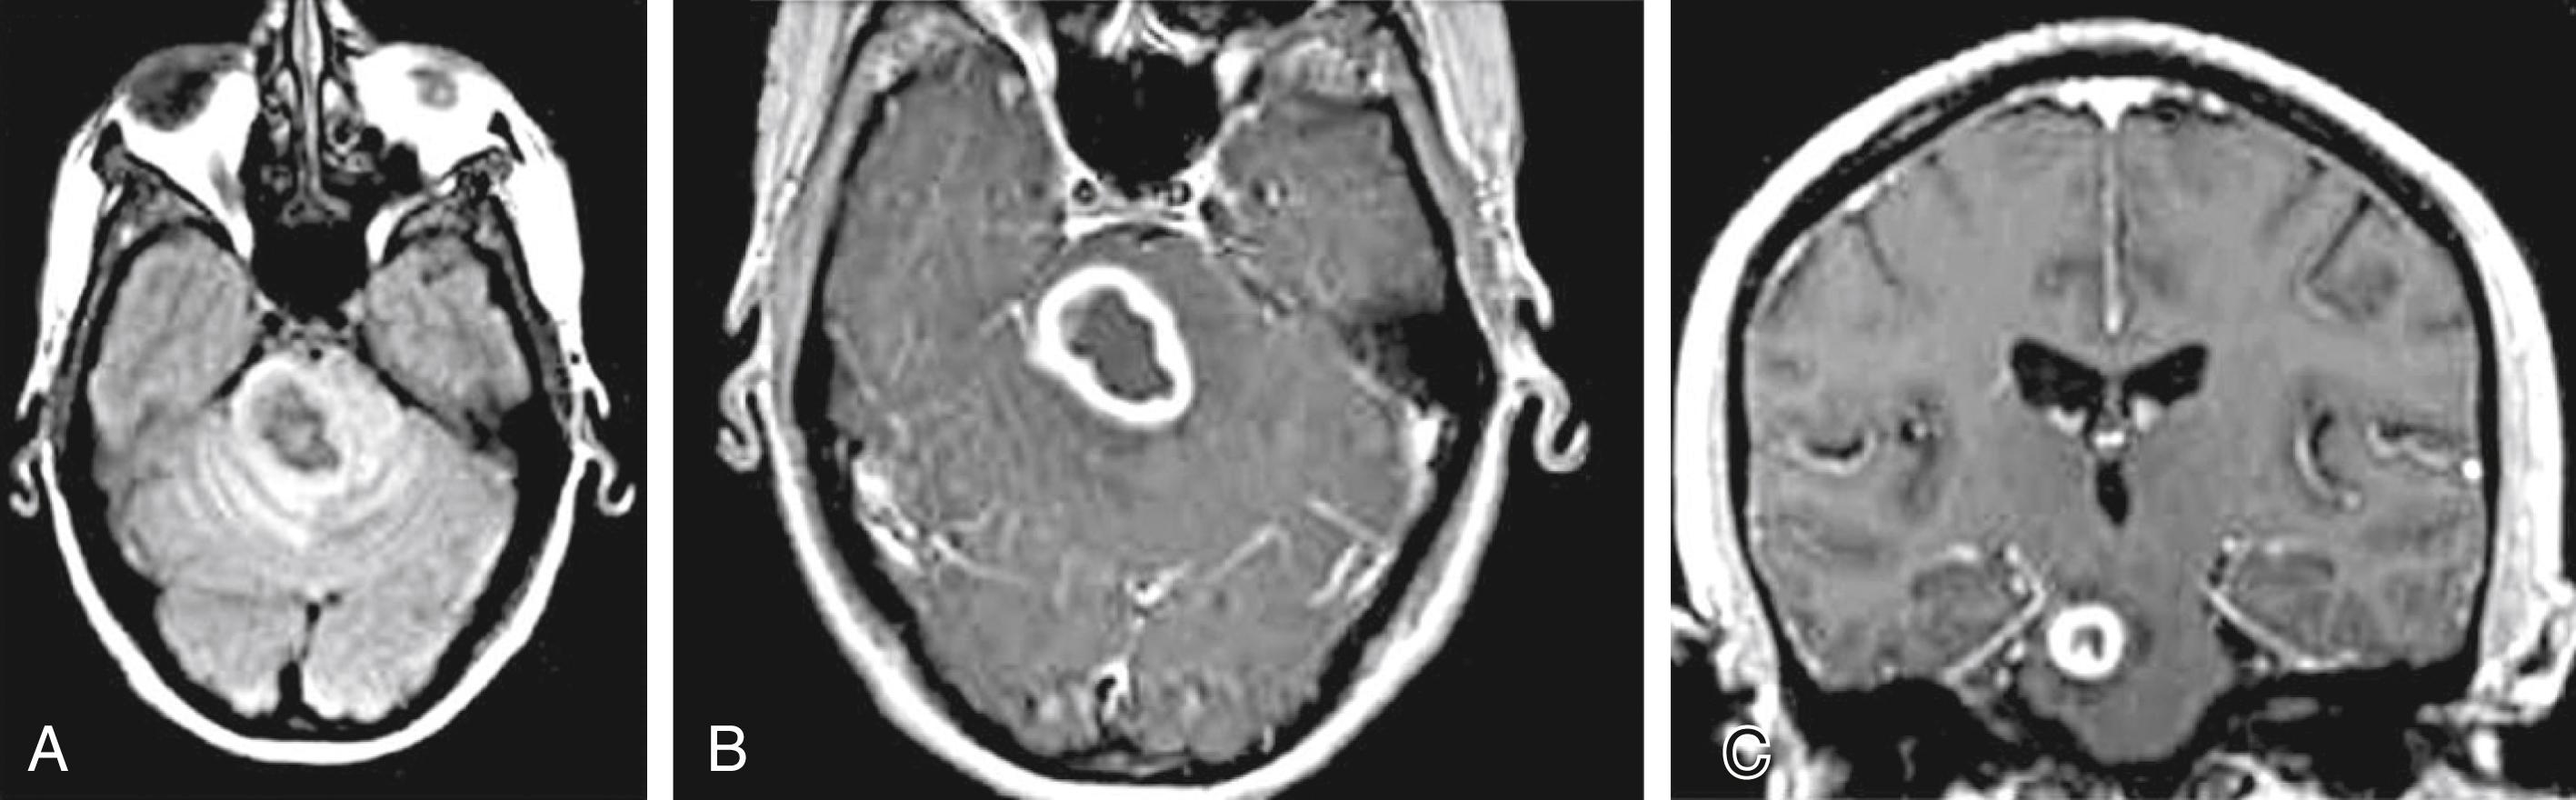

On MRI ( Fig. 40.21 ) glioblastomas usually exhibit mixed signal intensities on T1- and T2-weighted images. Cystic and necrotic areas are present, appearing as markedly decreased signal on T1-weighted and hyperintensity on T2-weighted images. Mixed hypo- and hyperintense signal changes due to hemorrhage are also seen. The hemorrhagic component can also be well demonstrated by gradient echo sequences or by SWI. The core of the lesion is surrounded by prominent edema, which appears hypointense on T1-weighted and hyperintense on T2-weighted images. Besides edema, the signal changes around the core of the tumor reflect the presence of infiltrating tumor cells and, in treated cases, postsurgical reactive gliosis and/or postirradiation changes. Following administration of gadolinium, intense enhancement is noted, which is inhomogeneous and often ringlike, also including multiple nodular areas of enhancement. The surrounding edema and ringlike enhancement at times makes it difficult to distinguish glioblastoma from cerebral abscess. DWI is helpful in these cases; glioblastomas are hypointense with this technique, whereas abscesses exhibit remarkable hyperintensity on diffusion-weighted images.

Fig. 40.21, Glioblastoma Multiforme.